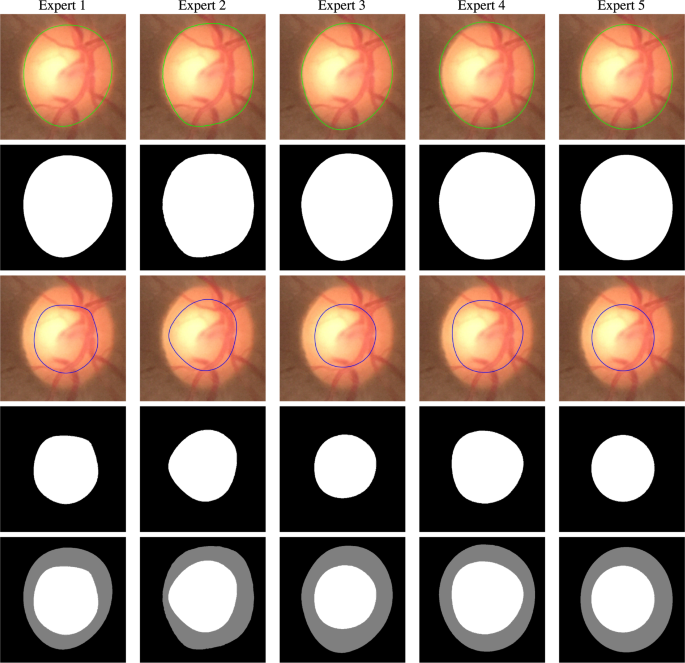

Five expert Indian ophthalmologists provided the OD and OC segmentation ground-truth and a binary decision on whether the subject is glaucomatous or not. Two of the experts are experienced Professors, two Associate Professors, and one is a clinical practitioner. Three of the experts are glaucoma specialists and two are general ophthalmologists, with experience ranging from 5 to 15 years. They are also coauthors of this paper. In order to overcome bias due to shape-specific (for instance, the tilted-ellipse) OD and OC annotation in some of the existing databases, our experts used smooth closed contours for manual delineation of the OD and OC. The annotation tool is based on ImageJ31,32, which is a widely used Java-based image processing program developed at the National Institutes of Health, USA. The experts specify several knot points (greater than 10) on the boundary of the OD/OC using ImageJ’s polygon selection tool. The points are connected using cubic B-spline interpolation. We used the cubic B-spline kernel as it possesses the minimum-curvature interpolation property33. The experts were given the flexibility to edit the knot locations, update the contour, and save the final outline. An illustration of the contours is provided in Fig. 2, wherein the OD and OC are shown in green and blue contours, respectively. The contours are used to arrive at a binary decision mask, which serves as the ground-truth for the OD and OC segmentation. Figure 3 shows the OD and OC outlines provided by the experts on a cropped fundus image together with their binary representations and fusion of expert OD and OC segmentation. In addition to the outline, the experts also provide binary glaucomatous/nonglaucomatous decisions, which are decided by a majority vote to arrive at a single decision per image.